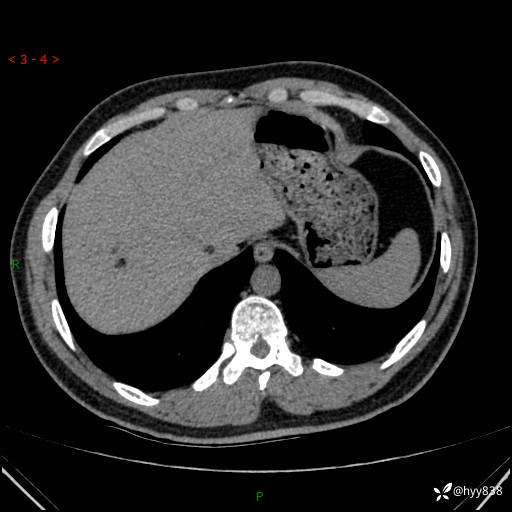

病例年轻小伙,早早的就切除了右侧肾脏,他怎么了---结果公布~

患者性别:男

患者年龄:28岁

简要病史:右肾肿瘤术后,常规复查

辅助检查:CT

临床诊断:右肾肿瘤术后

腹部CT+颅脑CT平扫